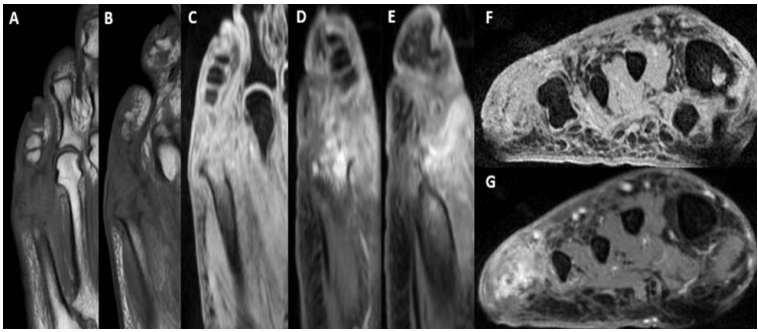

Figure 3: Follow up MRI

Select T1 and T2 images from contrast MRI performed one month later demonstrating worsening destruction of 5th metatarsal. Axial (A,B,C), Sagittal (D,E), Coronal (F,G).

Due to poor patient compliance, further radiographs and the MRI were performed 15 months after the first presentation [figure 1 - 2]. These showed complete bony destruction of proximal phalanx and metatarsal head with a 2 x 1cm collection in the lateral soft tissue [figure 2]. During this period, her symptoms had continued to fluctuate with the use of multiple antibiotics, including flucloxacillin, ciprofloxacin, metronidazole, co-trimoxazole and clarithromycin. The end result was the development of a discharging sinus, persistent swelling, localised erythema and pain. A month later a contrast MRI was performed to further delineate the lesion, which demonstrated no collection and a sinus tract in keeping with chronic infection [figure 3]. At three years following initial presentation, the symptoms worsened and the patient consented to surgical treatment consisting of amputation of the fifth toe at the level of the distal meta-diaphysis of the fifth metatarsal.